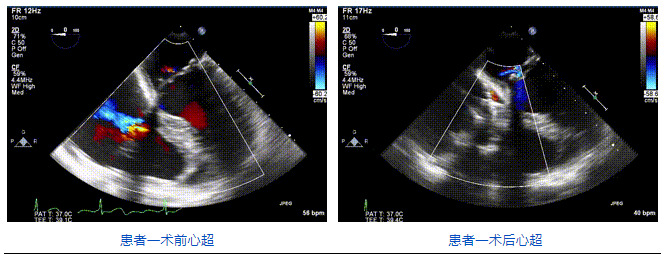

2021年12月24日,復(fù)旦大學(xué)附屬中山醫(yī)院葛均波院士團(tuán)隊(duì)成功應(yīng)用LuX-Valve Plus為一例極重度三尖瓣反流(TR)合并房顫、房缺的患者完成了經(jīng)血管三尖瓣置換術(shù),這是在前基礎(chǔ)上,本周完成的第三例經(jīng)血管三尖瓣置換手術(shù),葛均波院士、周達(dá)新教授等與心外科魏來教授、賴顥教授,心超室的潘翠珍教授、李偉教授及麻醉科的郭克芳教授共同完成了本周手術(shù),均獲得圓滿成功!患者術(shù)后超聲顯示無TR,臨床癥狀明顯改善。本周手術(shù)的成功也為LuX-Valve Plus救治性臨床研究添上了濃墨重彩的一筆。

三例患者入院后,葛均波院士團(tuán)隊(duì)周達(dá)新教授、潘文志教授、張?jiān)床┦?、陳莎莎博士及心超室的潘翠珍教授、李偉教授對患者的情況進(jìn)行詳細(xì)評估和討論,最終決定為三例患者選擇LuX-Valve Plus40mm、50mm和50mm型號的瓣膜進(jìn)行手術(shù)治療。手術(shù)后即刻拔除氣管插管,術(shù)后患者三尖瓣反流癥狀得到顯著改善,復(fù)查心超結(jié)果顯示人工三尖瓣瓣膜支架固定穩(wěn)定,瓣葉關(guān)閉形態(tài)未見異常,未見明顯反流。